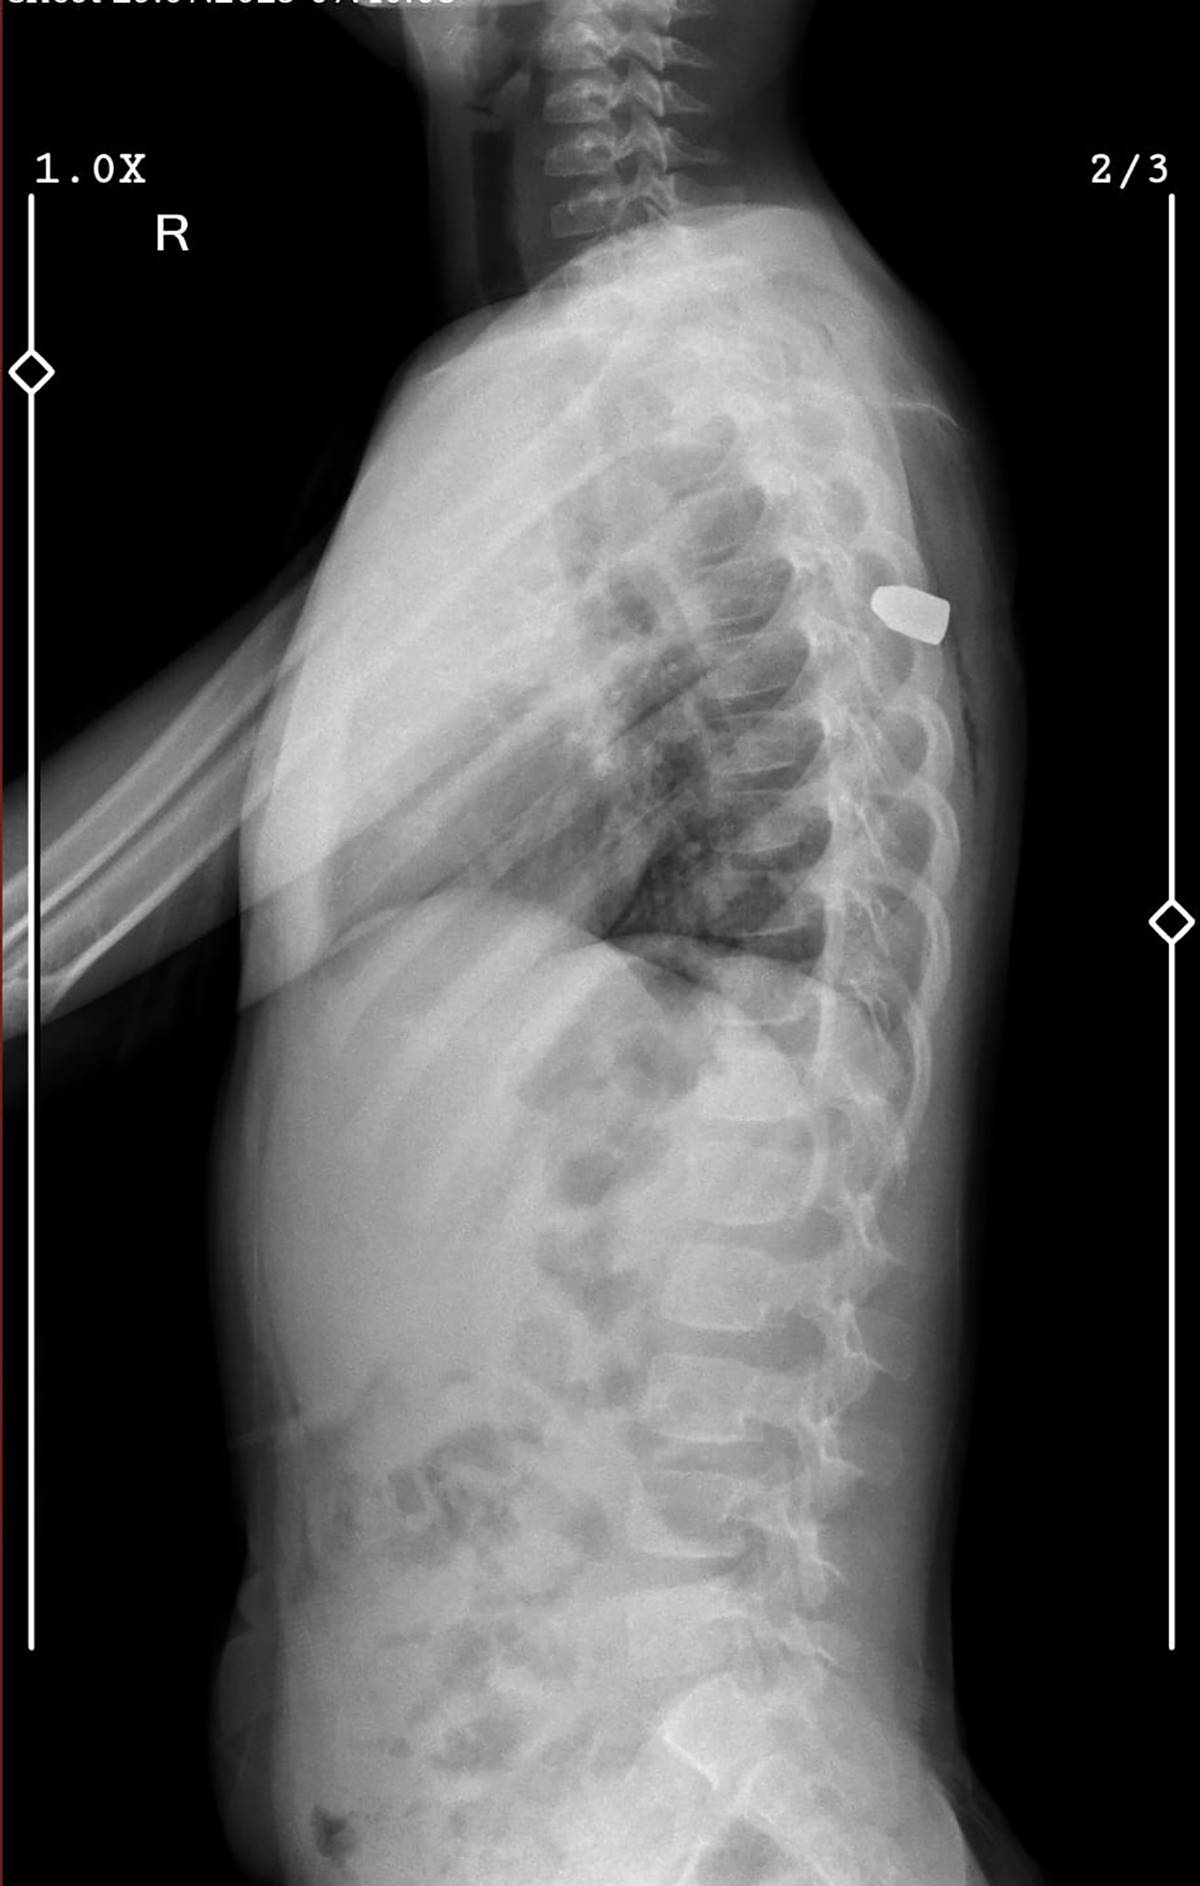

Hastanede röntgeni çekilen çocuğun sırtına mermi isabet ettiği belirlendi. Sırtındaki mermi ameliyatla çıkarılan çocuk daha sonra serviste gözetime alındı.